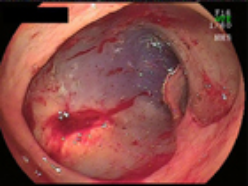

3.病変を取り去ったあとの胃と切除標本。胃の出口付近の粘膜のほとんどを剥離しました。

3.病変を取り去った後の直腸と切除標本。病変部の大きさはφ8cmでした。